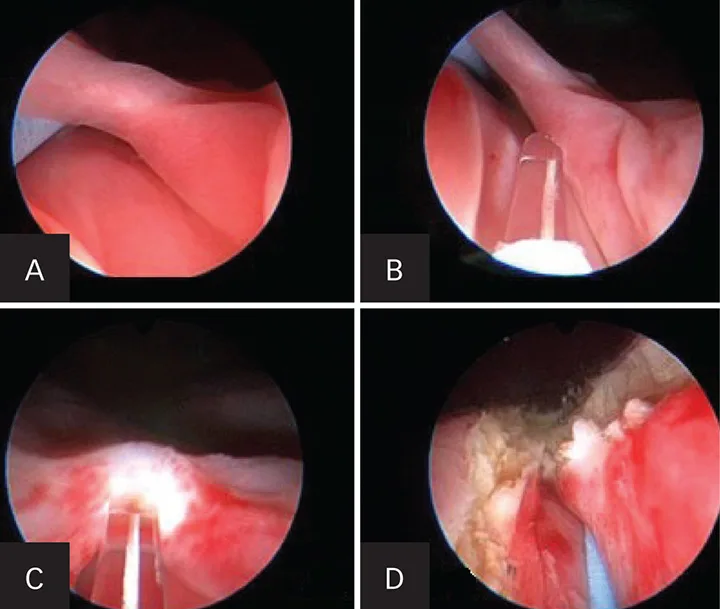

In humans, less invasive methods (eg, extracorporeal shockwave lithotripsy) have been shown to dramatically improve the preservation of renal function. Percutaneous nephrolithotomy (PCNL) can be markedly effective in removing all stone fragments in the calices. In addition, PCNL does not cause injury to the nephrons (Figure 1). Instead, the nephrons are spread apart with the use of a balloon dilation kit to allow a scope and intracorporeal lithotrite to remove the stone debris effectively. This has been shown in humans to be highly renal sparing and has been effective in the author’s practice.

Figure 1. Percutaneous nephrolithotomy in a 3.1-kg female Yorkshire terrier with large nephroliths. Use of a percutaneous access kit under fluoroscopic guidance allows visualization of the large nephrolith (asterisk; A). The access sheath (black arrowhead) is inserted through the renal parenchyma over a dilation balloon. Two safety wires (white arrows) are present. The nephroscope (white arrowhead) is inserted through the sheath onto the stone with a lithotrite, breaking the large stone into fragments (black arrowheads; B). Fluoroscopic image after all stone fragments had been removed from the renal pelvis (C). The nephroscope being placed through the access sheath during percutaneous renal access (D). An endoscopic image of the nephrolith taken during lithotripsy (E). The lithotrite (asterisk) is seen through the working channel of the nephroscope.